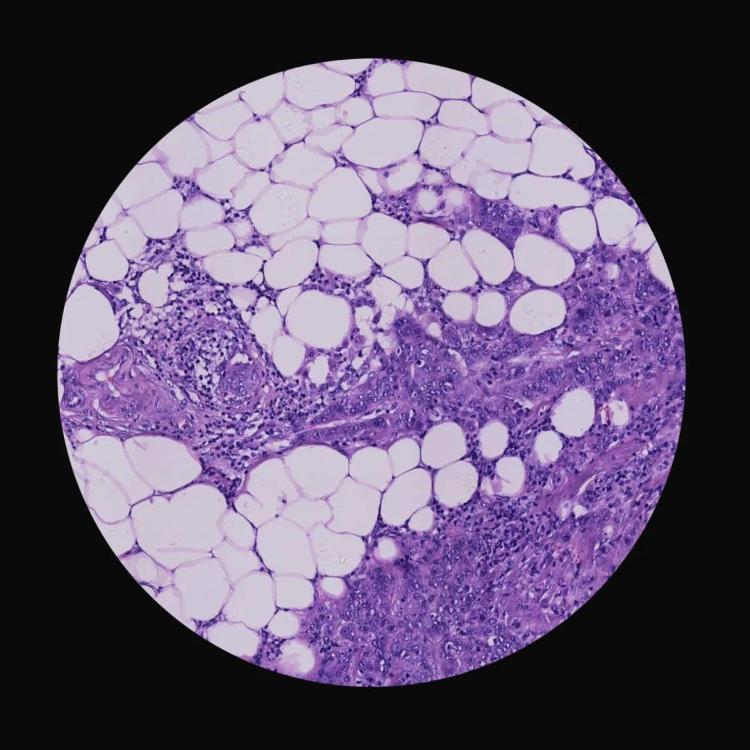

《生死较量》(组照) 李元鹏 摄影